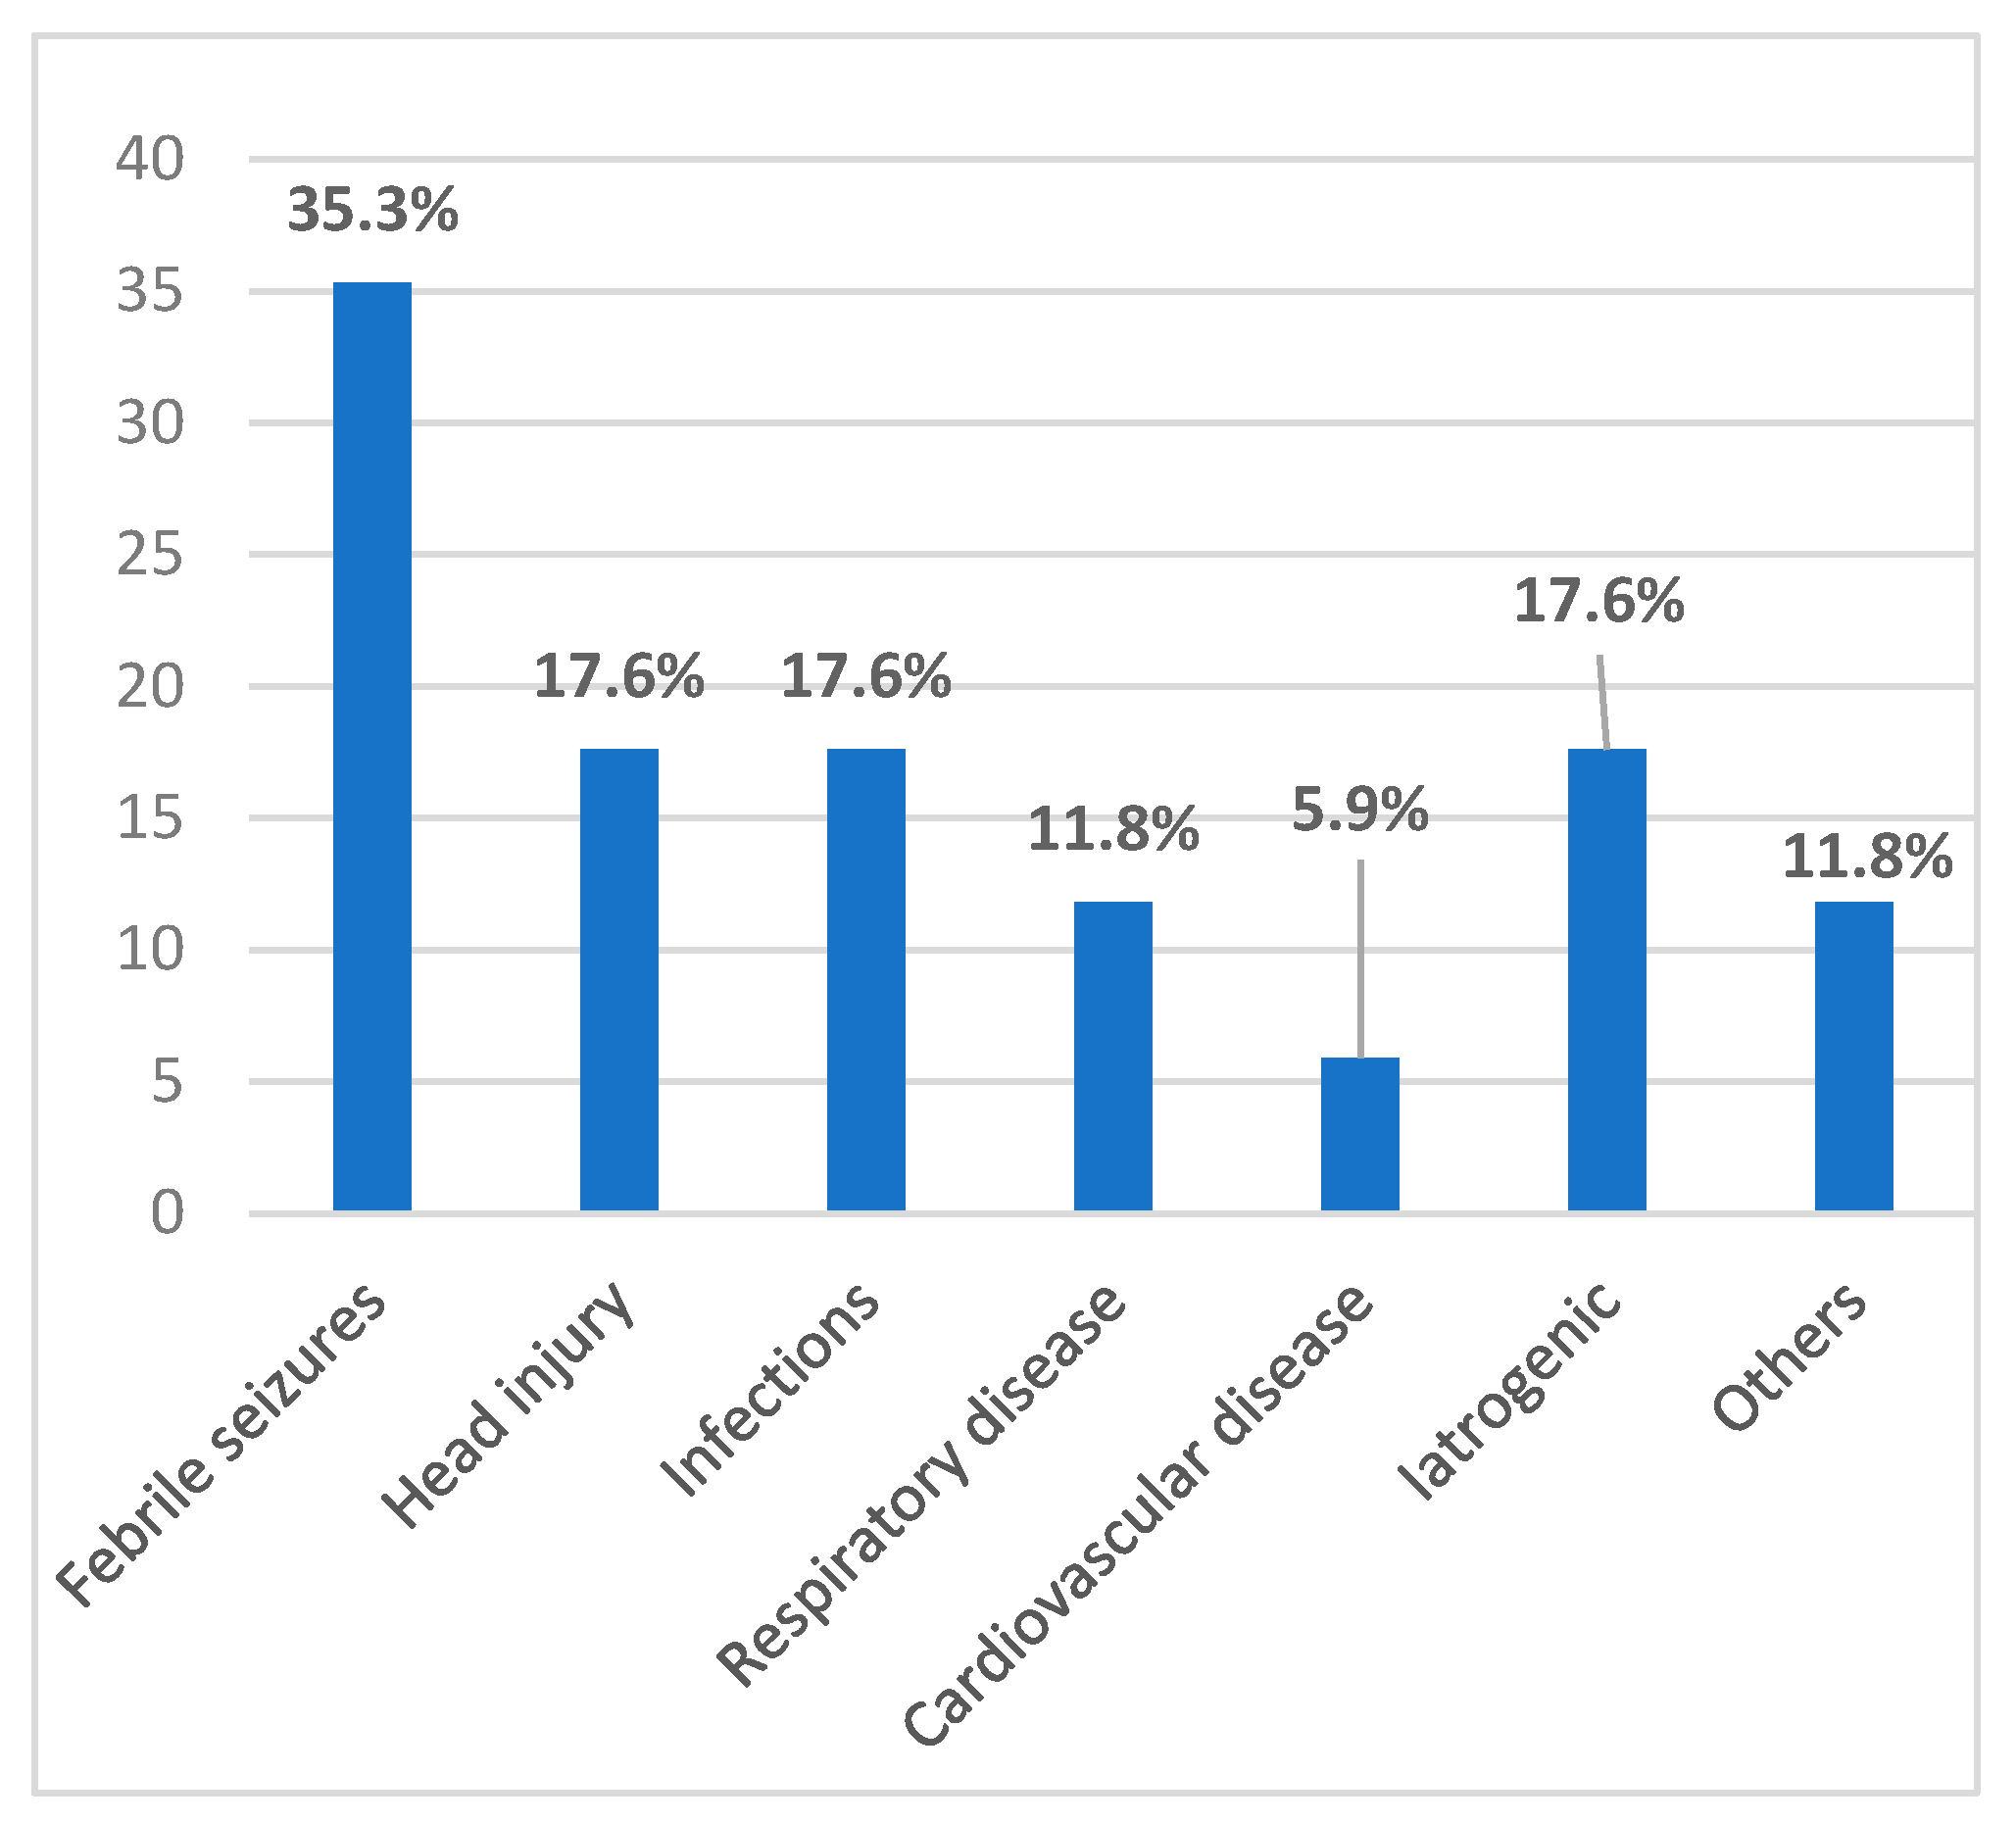

3.1. Prenatal, Perinatal, and Postnatal Risk Factors